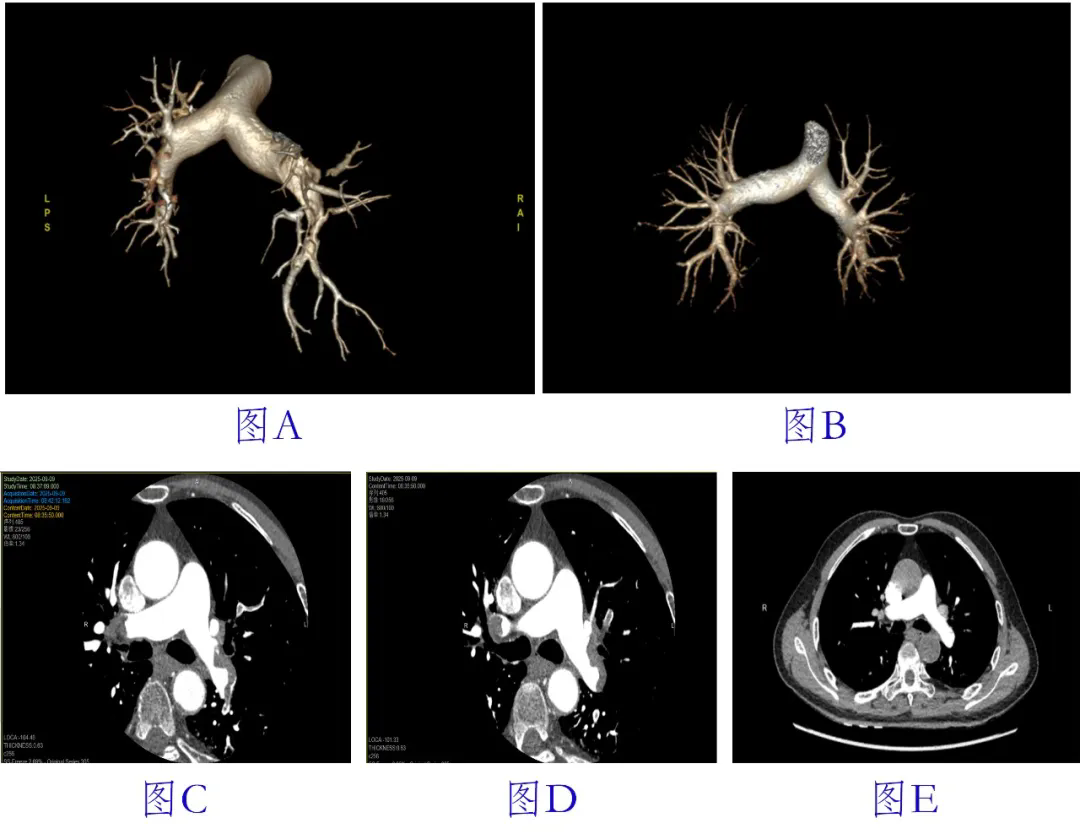

73岁的王先生(化名)平日坚持日行万步,身体硬朗,近日却突发活动后气促、呼吸困难,被诊断为“中危大面积肺栓塞”,经评估患者三十天内死亡风险超11%。给予两周规范抗凝与循序渐进的康复,最终顺利出院。抗凝治疗前后肺血管CTA对比显示治疗效果显著(图A、C、D为治疗前,B、E为治疗后)。